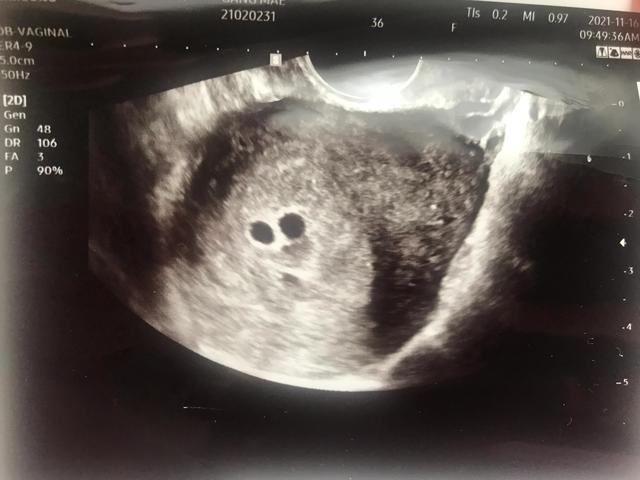

11月16日b超检查,又有1例孕囊双胎。我好害怕,好开心。惊喜过后,担心没看到胎心胎芽。我一周后再来检查!